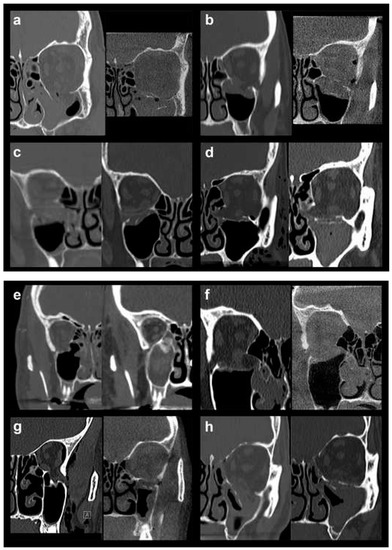

In order to allow for a valid statistical comparison between small and large defects, OFFs comprising Jaquiéry classes II to IV were merged into the “large defect” OFF group (28 patients, 45.9%). This collective category was statistically compared to the “small defect” OFF group represented by injuries classified as Jaquiéry I (33 patients, 54.1%), thus, up to 2 cm2. In Figure 1, pre- and postoperative conventional or cone-beam CT scans (coronal views) of all 7 class III fractures (Figure 1a–g) and 1 class IV fracture (Figure 1h) are shown.

Figure 1.

Pre- and postoperative conventional or cone-beam CT scans (coronal views) of all 7 class III fractures (a–g) and 1 class IV fracture (h).